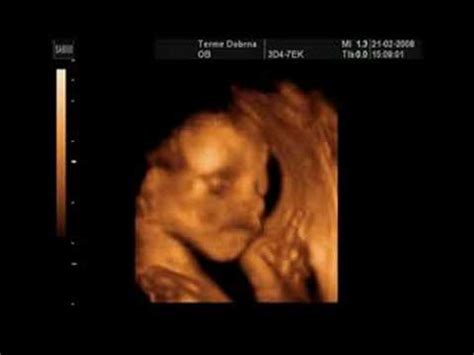

- Ultrazvočni posnetek: Pokažite ultrazvočni posnetek prijateljem ob kavi in opazujte njihove reakcije.